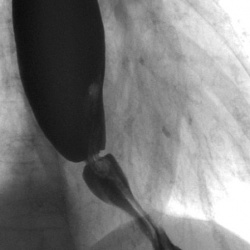

Возвращаясь к теме "кольца Шацкого".

Фрагмент функционального исследования пищевода.